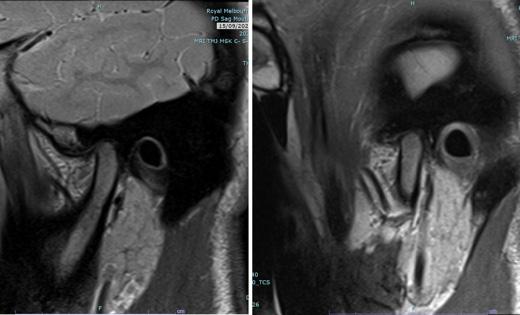

Treatment planning protocol was the same for all individuals and included examination, impressions for study models and a clinical bite record using wax and captured in centric relation (CR, the condyle was in the most superior and posterior position in the glenoid fossa). The clinical bite records and study models were subsequently digitised. A pre-operative medical-grade helical CT image was captured with the individual in a supine position with their lips closed, ensuring gentle occlusion in centric occlusion (CO, the position of maximum intercuspation of the dentition) without a bite registration splint. The CT protocol was derived from KLS Martin Group (KLS Martin Group, Germany) including special resolution of 0.5–1.25 mm and gantry tilt of 0°. A virtual skull model was created for each individual by a clinical engineer using Materialise Magics three-dimensional printing software (Materialise, Belgium). This process involved two steps with collaboration between the clinical engineer and the surgeon pivotal in forming the surgical plan, a dynamic process tailored to each patient’s unique requirements, outlined in Figure 1

2. Superimposed digital reconstruction skull images from Materialise Magics with the planned final outcome in orange and the post-operative scan data in green

Seventeen individuals (12 females, age range between 18 and 61 years) satisfied the inclusion criteria. The number of patients in each surgery type (maxillary, mandibular, bimaxillary) is presented in Figure 3

The disparities between the anticipated positions of selected landmarks and their actual post-operative locations in both singlejaw and bimaxillary surgeries are summarised in Table 2

For the maxillary surgeries, the mean combined difference between anticipated movements and final position along the x, y and z axes was compared between single-jaw (1.33 ± 1.12 mm) and bimaxillary surgeries (1.33 ± 1.30 mm), as seen in Figure 4. An independent samples t-test revealed no statistically significant difference between single-jaw and bimaxillary surgeries (t(210) = 0.01; P = 0.992). The mean combined difference between anticipated movements and final position along the x, y and z axes in the mandible for single-jaw (1.00 ± 1.20 mm) and bimaxillary surgeries (1.75 ± 1.47 mm) was calculated (Figure 5). An independent samples t-test indicated a significant difference (t(257) = 4.91; P < 0.001; d = 0.54).

Three-dimensional linear measurements ranged between a mean of 0.86 mm for the lower right mandibular molar in single-jaw surgery

and 5.75 mm for the pogonion in bimaxillary surgery. Levene’s test did not reveal any statistically significant difference among the variances of the maxillary landmarks in either single-jaw or bimaxillary surgeries (single jaw: F(5, 84) = 0.53, P = 0.752; bimaxillary: F(5, 138) = 0.37, P = 0.871). However, a significant difference was noted between mandibular landmarks in both single-jaw and bimaxillary surgeries (single jaw: F(8, 88) = 4.85, P < 0.001; bimaxillary: F(8, 207) = 2.96, P = 0.004). A significant difference in variance occurred between single-jaw and bimaxillary surgeries in the mandible (F(1, 322) = 7.93; P = 0.005), but not in the maxilla (F(1, 232) = < 0.001; P = 0.996) and not between the maxilla and mandible in single-jaw operations (F(1, 196) = 2.57; P = 0.110) or bimaxillary operations (F(1, 358) = 1.51; P = 0.220). There was a heterogeneic variance among the x, y and z axes in the maxilla in both single and bimaxillary surgeries (single jaw: F(2, 87) = 6.50, P = 0.002; bimaxillary: F(2, 141) = 6.28, P = 0.002), but not in the mandible (single jaw: F(2, 105) = 0.13, P = 0.883; bimaxillary: F(2, 213) = 0.32, P = 0.729).

This article shows that this simplified method of VSP assessment results in a clinically accurate assessment for orthognathic surgery. The accuracy from the planning protocol is derived from segmentation of the CT imaging to incorporate digitised scanned occlusion. Deviations from this position could pose challenges for clinical engineers in determining the correct condylar position, leading to a notable variance between the planned and actual outcome for CoR

and CoL points. Accurate data collection before formulating the surgical plan, including the capture of impressions and centric relation clinically is crucial, as any errors in this phase would propagate through the planning process. This simplified protocol not only achieves clinically acceptable outcomes but also improves surgical and pre-operative efficiency by reducing technique sensitivity, requiring only one consultation appointment, eliminating the need for guide splints, and streamlining the process with a single preoperative radiographic scan.

Most mean landmark variances, except for three, and all median values except one, remained below the 2-mm threshold recognised as clinically significant.19 The findings of this study demonstrate favourable outcomes in the maxilla, both for singlejaw and bimaxillary surgeries, with greater accuracy of maxillary landmark positions (mean, 1.09–1.51 mm). Therefore the maxillary position on the CT scan is not influenced by the position of the condylar seating at the time of the scan. In contrast, the mandibular movements had greater variations in the accuracy of landmark positioning. Landmarks anterior to the osteotomy in the proximal segment of single-jaw surgery (B, mandibular mid-incisor point [Md], Pog) exhibited minimal variance between their planned and actual postoperative positions (mean, 0.43–0.61 mm). However, the points in the distal segment (CoL, CoR, GoL, GoR, lower left first molar [LLM], lower right first molar [LRM]) had larger discrepancies (mean, 1.21–2.34 mm). Notably, GoL exceeded the 2-mm threshold for clinical acceptability.19 This may be explained by intraoperative seating of the condyle being potentially varied from the predicted seating of VSP; influenced by soft tissues within the temporomandibular joint, perimandibular musculature, alignment of the lower border of the mandible and control of torsional movements of the proximal segment.

During bimaxillary surgery, the mandible exhibited the highest degree of variance, particularly at Pog (2.89 mm) and GoL (2.19 mm) and GoR (1.62 mm). This is expected due to the compounded nature of any discrepancy from the initial maxillary movement and fixation position before mandibular movement. Previous studies